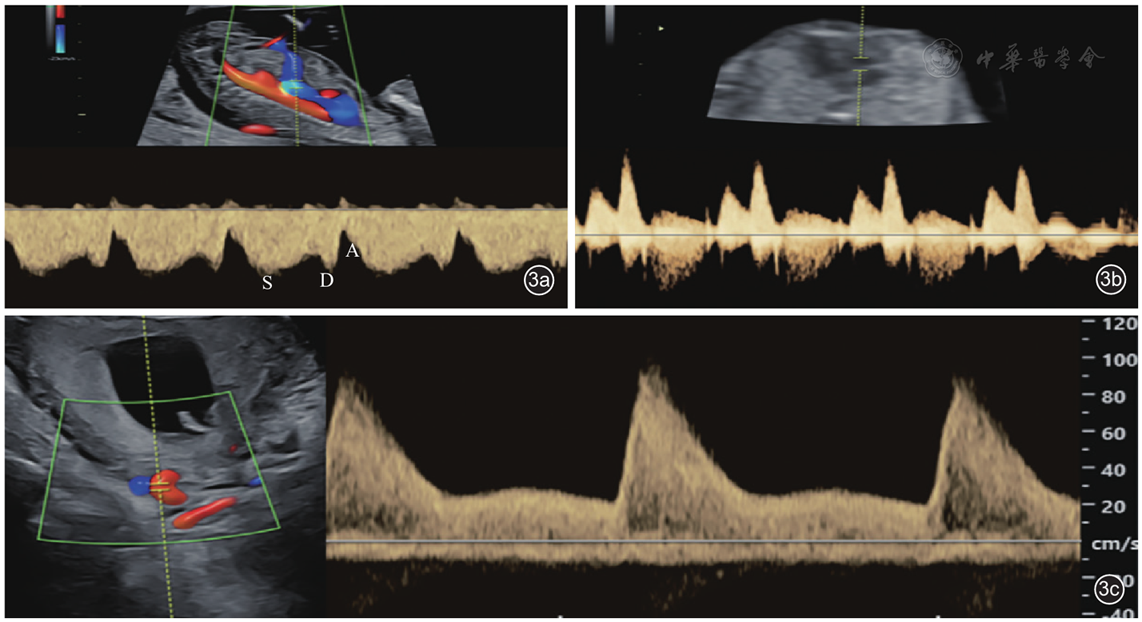

13.静脉导管血流(图3a):

图3 11+0~14+0周胎儿多普勒超声检查中相关生物学测量。图a:胎儿胸腹部旁矢状切面静脉导管多普勒频谱;图b:心脏四腔心切面三尖瓣多普勒频谱;图c:子宫动脉多普勒频谱

静脉导管通常在右侧旁正中矢状切面进行评估。研究表明静脉导管a波反向与非整倍体之间存在相关性[3,4]

14.三尖瓣血流(图3b):

通常于心尖位于12点或6点方向时的四腔心切面评估,2~4 mm取样框置于三尖瓣上获取波形。三尖瓣反流定义为血流>60 cm/s,时间超过半个心动周期。

UtA-PI标准化测量要求在子宫矢状面上识别宫颈内口,然后保持探头位置不变,轻轻向两侧倾斜,使用彩色多普勒在宫颈内口水平沿着宫颈和子宫边缘来识别两侧子宫动脉(图3c)。使用脉冲多普勒(取样框为2 mm,声束角度<30°)获得3个以上相似的连续波形,使用自动跟踪测量UtA-PI并计算平均搏动指数。当无法测量UtA-PI和(或)PlGF时,基础筛查应该是母体因素与MAP的组合,而不是单独的母体因素。